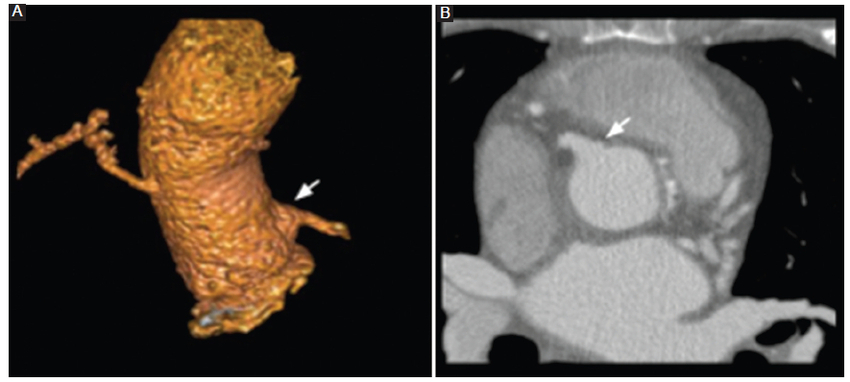

Cirugía de Ross

Esta operación fue ideada para implementarse en niños porque el autoinjerto pulmonar crece con el niño, aunque también puede ser utilizada en pacientes de cualquier edad6.

En el procedimiento de Ross, la válvula aórtica nativa y la raíz aórtica son reemplazadas a 1 cm distal al origen de la arteria coronaria derecha, lo que a su vez permite inspeccionar el estado de la válvula aórtica, la raíz aórtica y el tracto de salida del ventrículo izquierdo durante el acto quirúrgico7. La válvula pulmonar y la porción proximal de la arteria pulmonar del propio paciente se fijan al tracto de salida del ventrículo izquierdo y al anillo aórtico con múltiples suturas de poliéster. A esta arteria aorta tratada se le reimplantan las arterias coronarias, las cuales serán reubicadas en función de la válvula, pudiendo ser esta última subcoronaria, subcoronaria con preservación del seno no coronario, cilíndrica o raíz completa. Finalmente, se restablece el flujo de la arteria pulmonar a través de un injerto sintético o bioprotésico (Figs. 5 y 6) (6,7.

Al igual que otros procedimientos, la cirugía de Ross puede tener complicaciones, entre las que se mencionan el aumento de la regurgitación aórtica y la dilatación progresiva del autoinjerto pulmonar como principales limitaciones6,7.